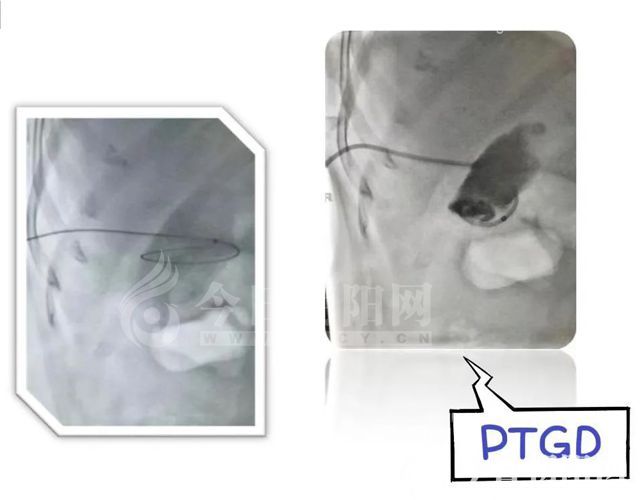

對于身體情況差且患有急性梗阻性化膿性膽管炎的高齡患者, 醫(yī)院會先采用行經(jīng)皮肝膽管穿刺(PTCD)或經(jīng)內(nèi)鏡鼻膽管引流術(shù)(ENBD)治療,待患者病情穩(wěn)定后再行下一步手術(shù),循序漸進,科學制訂治療方案,在臨床實踐中取得了良好效果。

考慮到患者高齡、基礎(chǔ)疾病復(fù)雜、手術(shù)耐受能力差,做膽囊切除+膽道探查的傳統(tǒng)手術(shù)風險大,醫(yī)院建議急診行經(jīng)皮肝膽囊穿刺或經(jīng)皮肝膽管穿刺引流術(shù),待病情穩(wěn)定后,擇期處理原發(fā)病?;颊呒覍俦硎纠斫?。手術(shù)過程順利,患者腹痛緩解,尿量增多,體溫趨于正常。1周后帶管出院。

北票市中心醫(yī)院普外科開展PTCD、ENBD項目2年來,在梗阻性黃疸患者的減黃、膽道惡性腫瘤的姑息性治療(膽道支架),以及經(jīng)十二指腸鏡奧迪氏括約肌切開取石方面積累了一定經(jīng)驗,以精湛醫(yī)術(shù)結(jié)合先進醫(yī)療技術(shù)為病人解除痛苦,挽救了一個又一個寶貴的生命,為百姓高質(zhì)量就醫(yī)提供了更多選擇。